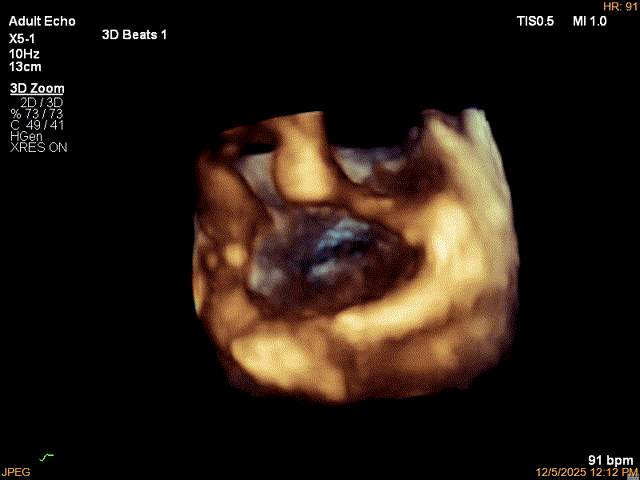

3D-Zoom下观察组织桥稳定,内侧残余脱垂

最终结果3D-Zoom-color显示组织桥稳定,原脱垂区域前后叶对合部分的脱垂已消除,反流降至1+以下

夹子释放Bi-com切面显示残余反流情况

肺静脉收缩期逆流消失,频谱形态基本恢复正常